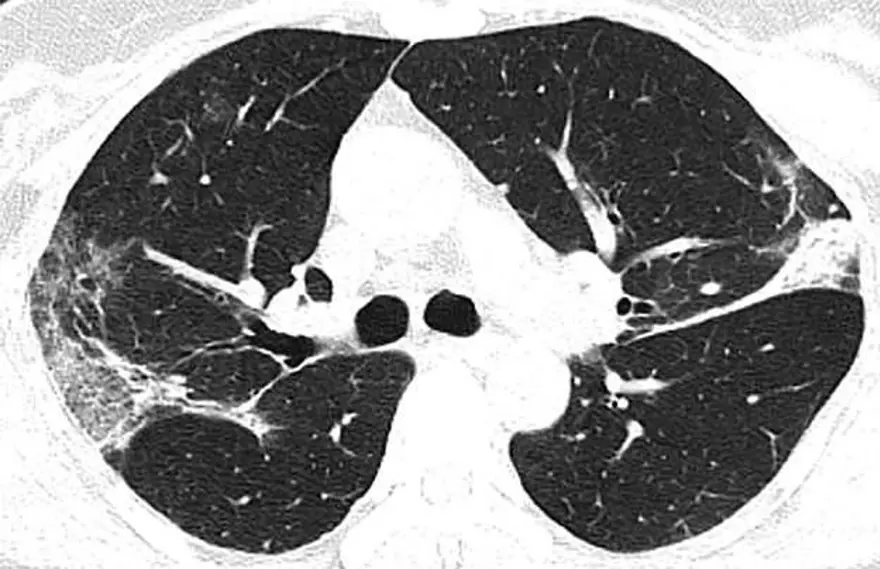

Çin'in Hubey eyaletine bağlı Wuhan’daki salgının kaynağı olduğu düşünülen hayvan pazarında çalışan 44 yaşındaki bir Çinlinin röntgen filmleri yeni tip corona virüsün akciğerlere verdiği zararı açıkça gösteriyor. Filmlerde akciğerdeki hava boşluklarının çoğunluğunun virüs nedeniyle dolduğu görülüyor. Uzmanlar, taramalarda görülen beyaz lekelerin SARS ve MERS’te de mevcut olduğunu belirtti.

Kuzey Amerika Radyoloji Derneği (RSNA), yeni tip corona virüsün (Covid-19) ortaya çıktığı Çin’in Wuhan kentindeki salgının kaynağı olduğu düşünülen deniz ürünleri pazarında çalışan ve 44 yaşında virüs nedeniyle hayatını kaybeden bir adamın röntgen filmlerini kamuoyuyla paylaştı. Filmlerde corona virüsün akciğerleri nasıl tahrip ettiği net bir şekilde görülüyor.

HAVA KESECİKLERİ DOLUYOR

X-ray ışını taramalarında corona virüsün etkileği yerler beyaz olarak görülüyor. Uzmanlar, hastada virüsün akciğerlerdeki hava keseciklerini kısmen doldurduğunu ve akciğer nodüllerine sebep olduğunu belirtti. .Diğer taraftan aynı tip anormalliklerin SARS (Şiddetli Akut Solunum Sendromu) ve MERS (Ortadoğu Solunum Sendromu) vakalarında da görüldüğünü söylediler.

Röntgenleri paylaşılan adamın yaklaşık iki hafta boyunca ateş ve öksürük belirtileri göstermesinin ardından 25 Aralık 2019'da hastaneye kaldırıldığı bir hafta sonra ise hayatını kaybettiği açıklandı.